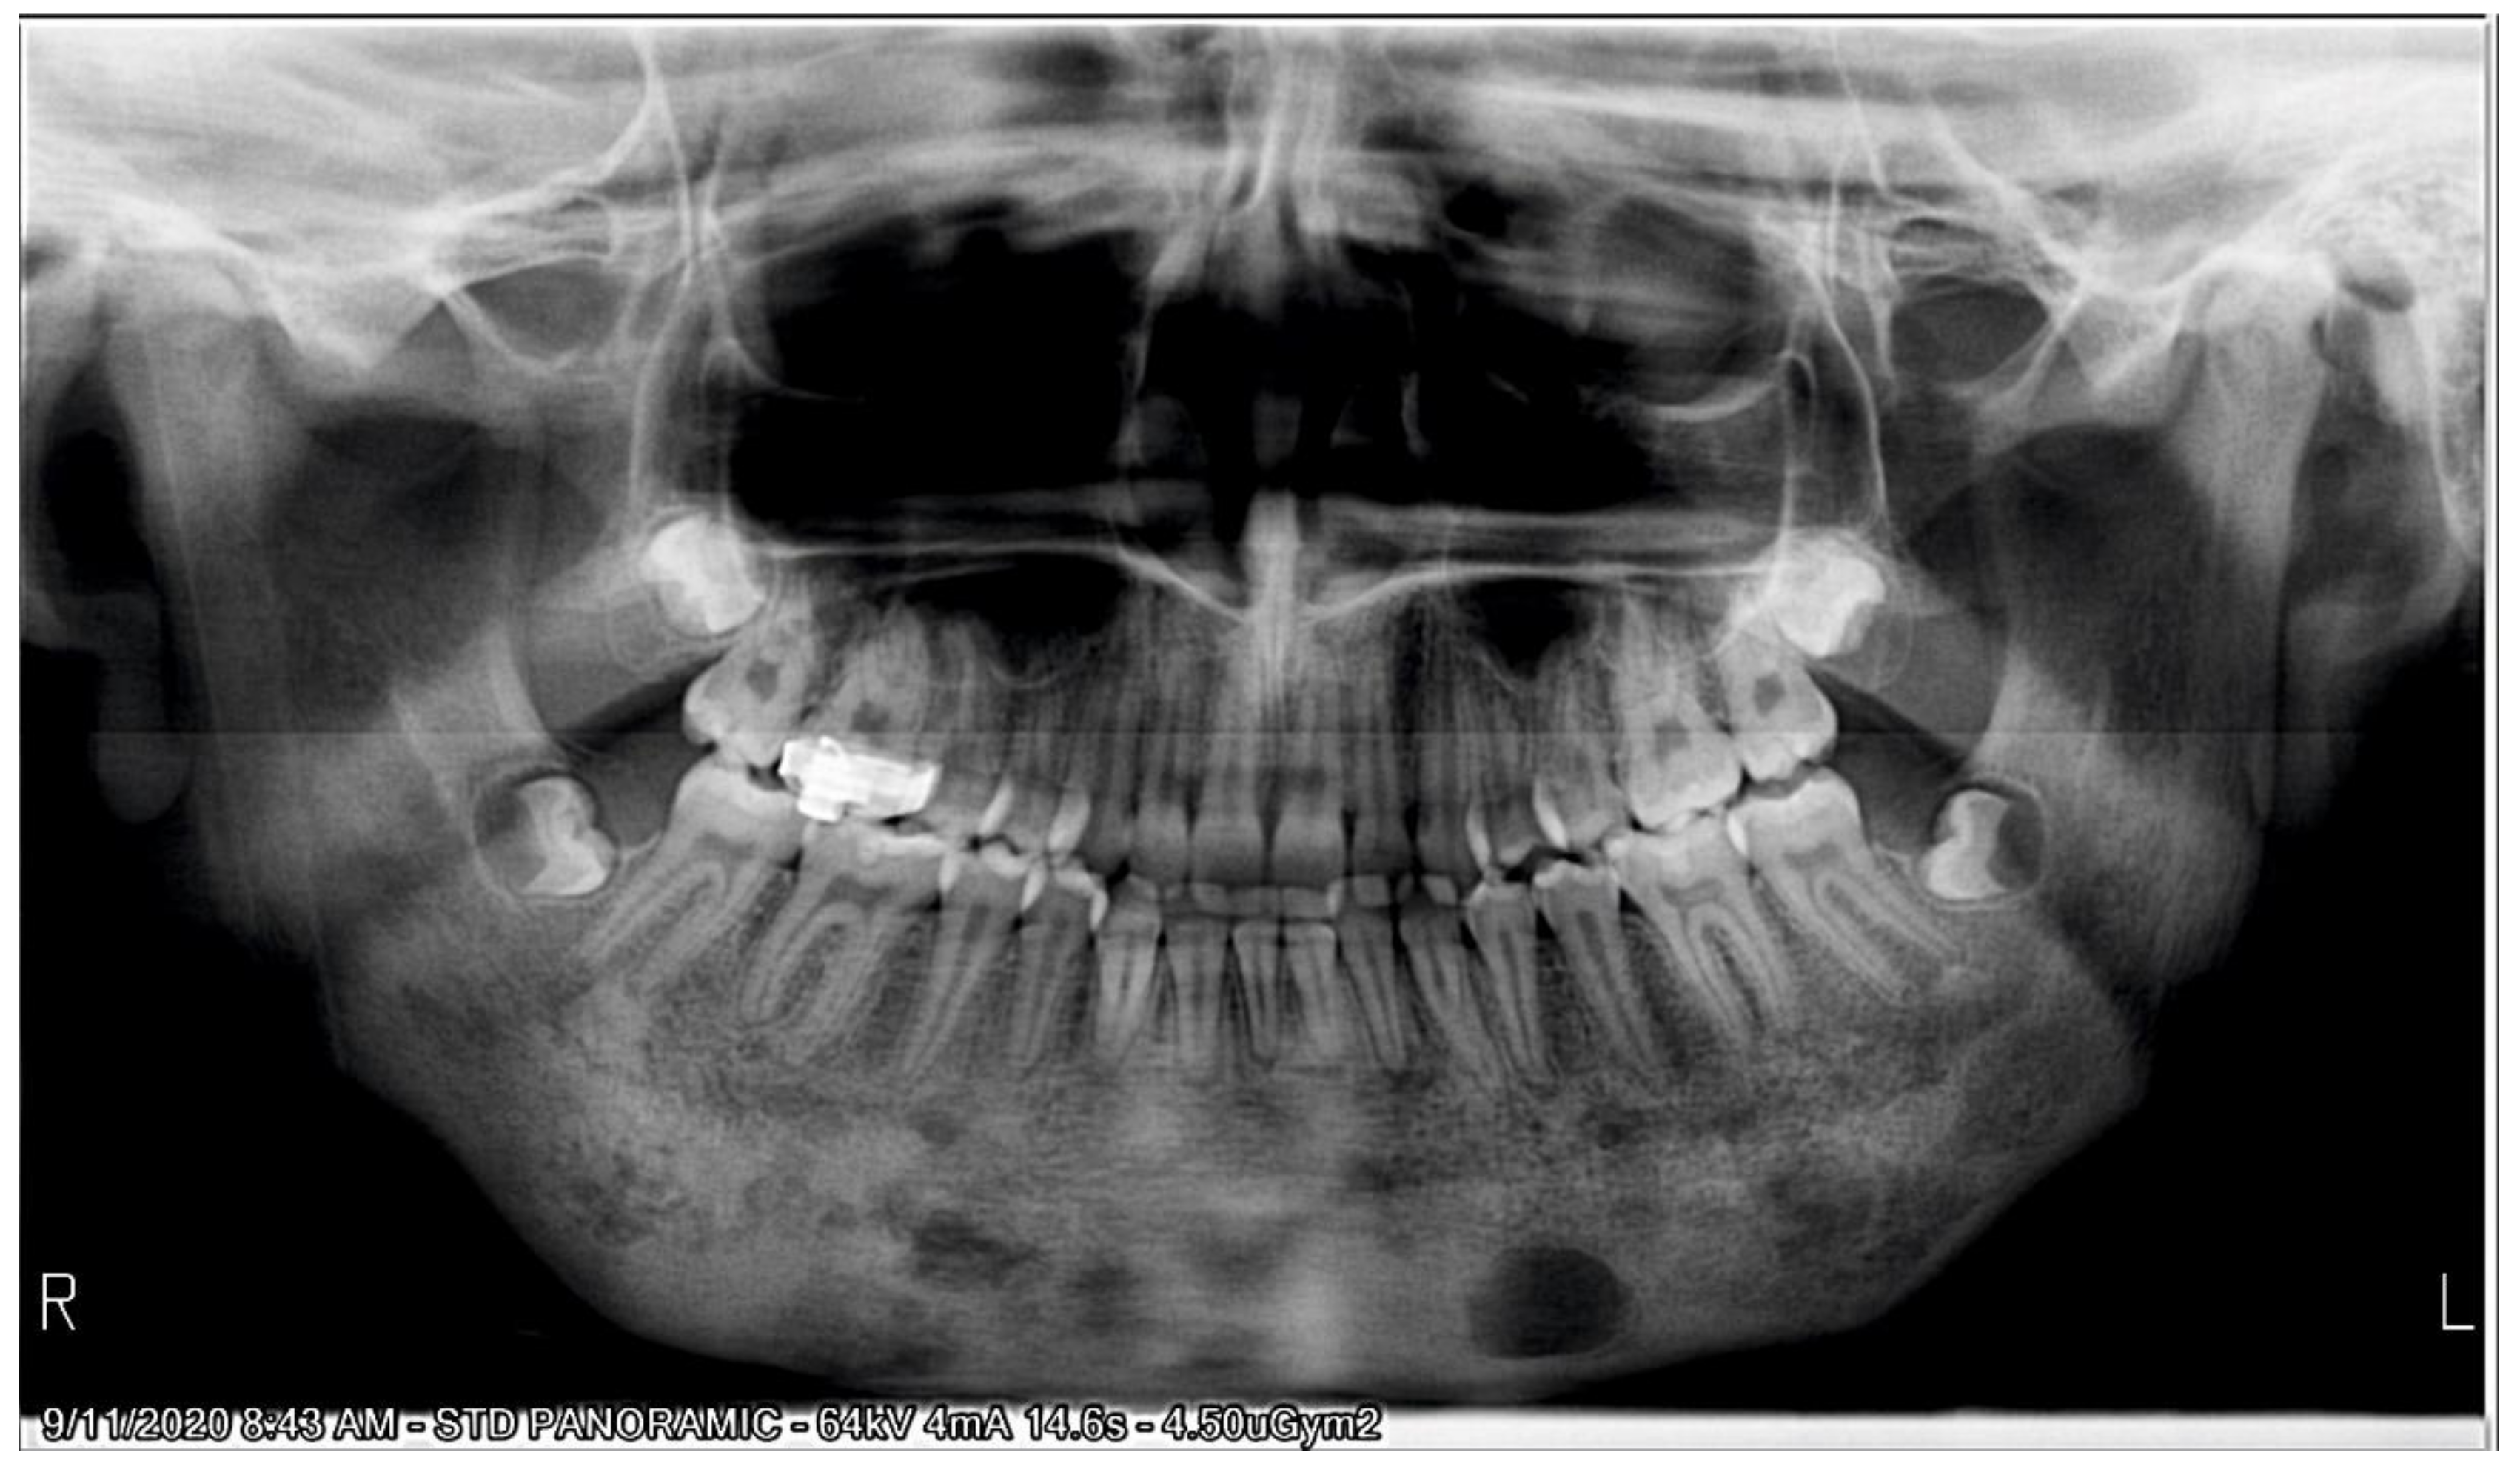

Garre's Osteomyelitis Radiographic Features . The radiographic appearance of periostitis ossificans. In general, the function of the affected bone is preserved. 5 the radiographic features include cortical thickening and loss of medullary canal. Garre's osteomyelitis is a local thickening of the periosteum caused by a slight irritation or infection. Raised inflammatory markers, negative tissue culture and radiological findings in our patient are common features in sclerosing osteomyelitis. Chronic osteomyelitis with proliferative periostitis, known as garre’s osteomyelitis, is a type of osteomyelitis. Apart from the typical onion skin appearance, po shows various other radiographic appearances. Radiological differential diagnosis of po includes infantile cortical hyperostosis, ewing's sarcoma, and osteosarcoma; We aimed to present the extraoral, intraoral, and. None of which fitted the clinical.

Radiological differential diagnosis of po includes infantile cortical hyperostosis, ewing's sarcoma, and osteosarcoma; Garre's osteomyelitis is a local thickening of the periosteum caused by a slight irritation or infection. 5 the radiographic features include cortical thickening and loss of medullary canal. Apart from the typical onion skin appearance, po shows various other radiographic appearances. Chronic osteomyelitis with proliferative periostitis, known as garre’s osteomyelitis, is a type of osteomyelitis. We aimed to present the extraoral, intraoral, and. None of which fitted the clinical. In general, the function of the affected bone is preserved. Raised inflammatory markers, negative tissue culture and radiological findings in our patient are common features in sclerosing osteomyelitis. The radiographic appearance of periostitis ossificans.

Garre's Osteomyelitis Radiographic Features In general, the function of the affected bone is preserved. None of which fitted the clinical. Chronic osteomyelitis with proliferative periostitis, known as garre’s osteomyelitis, is a type of osteomyelitis. 5 the radiographic features include cortical thickening and loss of medullary canal. Radiological differential diagnosis of po includes infantile cortical hyperostosis, ewing's sarcoma, and osteosarcoma; We aimed to present the extraoral, intraoral, and. In general, the function of the affected bone is preserved. Raised inflammatory markers, negative tissue culture and radiological findings in our patient are common features in sclerosing osteomyelitis. The radiographic appearance of periostitis ossificans. Garre's osteomyelitis is a local thickening of the periosteum caused by a slight irritation or infection. Apart from the typical onion skin appearance, po shows various other radiographic appearances.